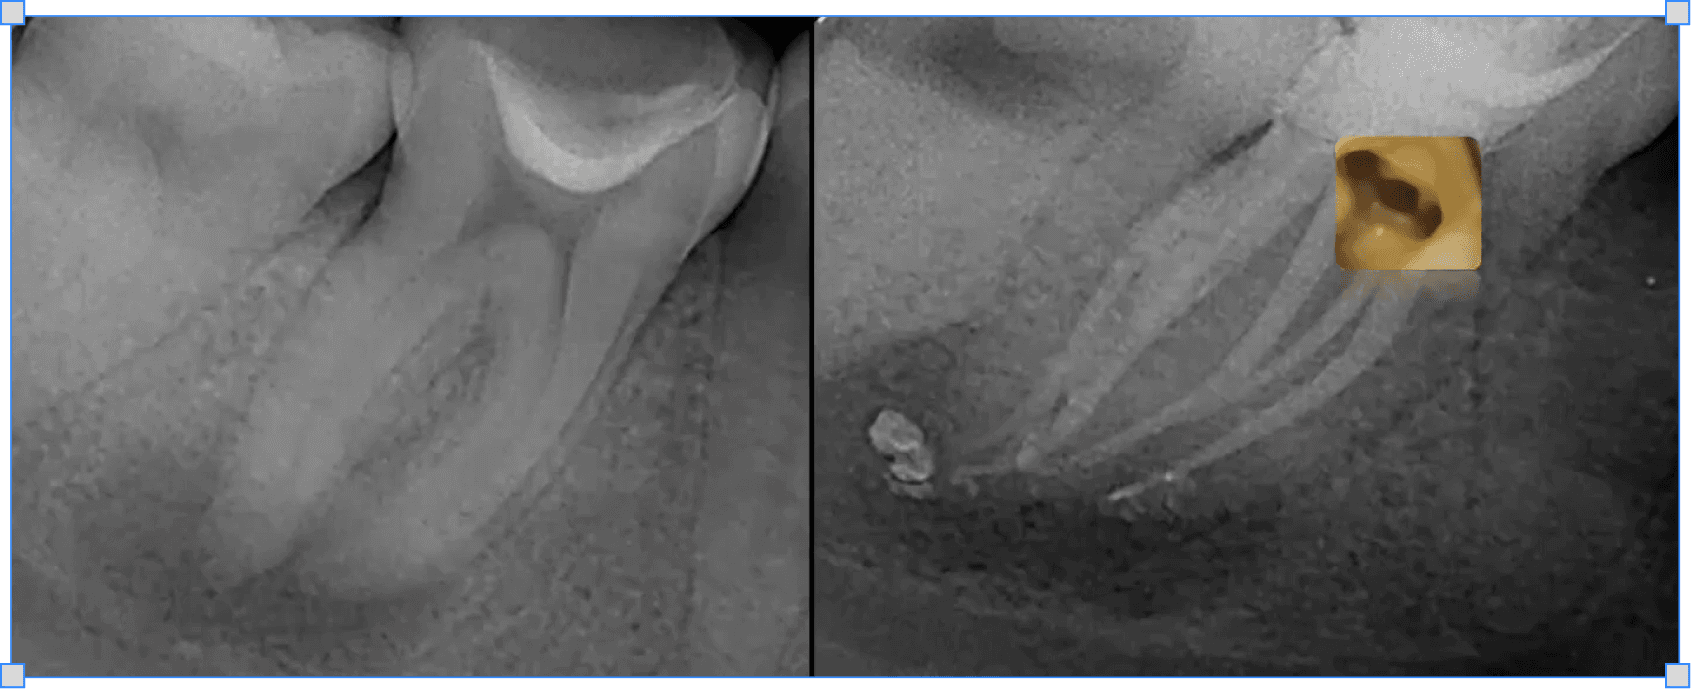

Станіслав Геранін

Все про

резорбції

Сучасна класифікація резорбтивних уражень

Основні критерії оцінки прогнозу та методів лікування

Лікування перфоруючих внутрішніх та комбінованих резорбцій